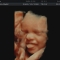

4d baby scan for pregnant women Baby moments https://www.scan4d.co.uk/ is a private pregnancy clinic both owned and run by professional, dedicated sonographers who thrive in the 4D baby scan, 4D ultrasound and pregnancy services that they offer to pregnant women and their families. We offer 4D/3D scan services. These scans are a once in a lifetime opportunity to spend quality time viewing your baby move, yawn, suck his/her thumb and sometimes smile. All this will truly touch your heart. We us